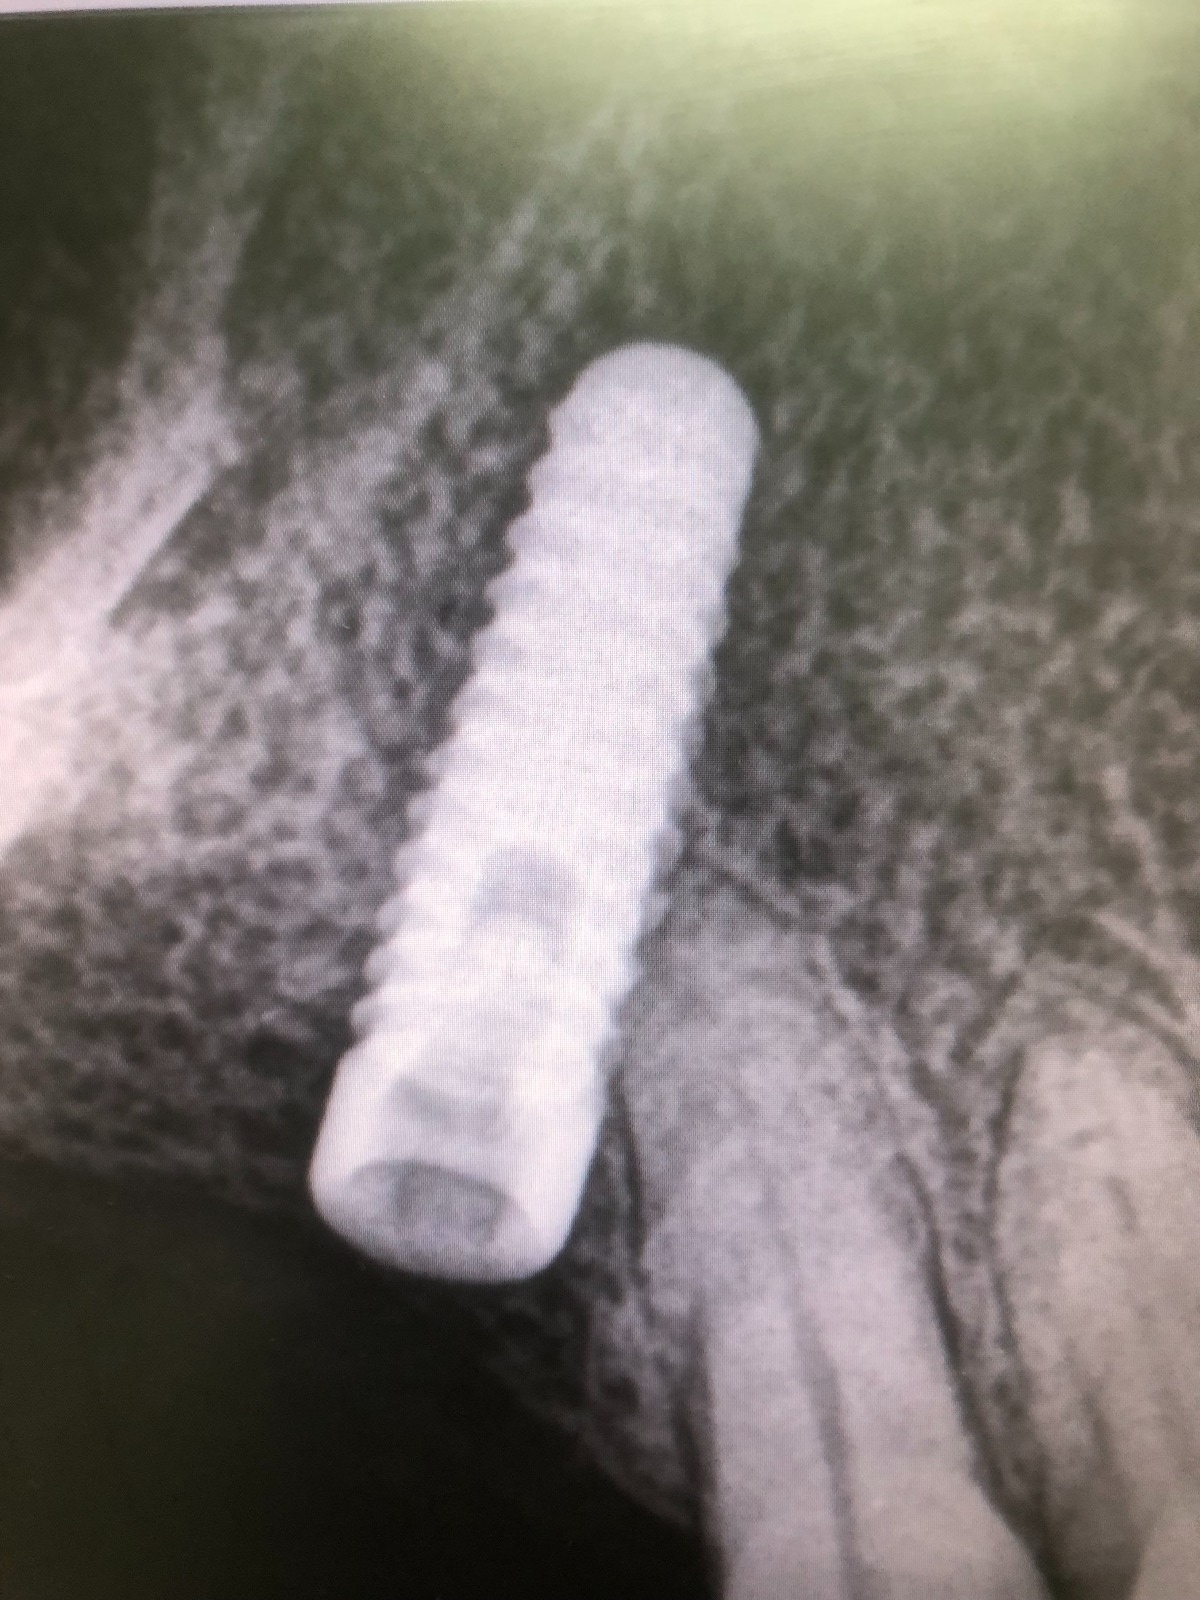

Como hemos comentado es un molar, es decir, una pieza dental en la zona posterior de la boca y con una posición del implante muy inclinada para poder esquivar el seno maxilar, lo cual dificulta mucho el trabajo.

Exponemos nuevo caso de paciente con una fractura del tornillo pasante sobre un implante unitario molar. El tornillo pasante es la parte fundamental de la conexión y es el que está roto dentro y gripado, de tal forma que no pudimos extraer con el aparato de ultrasonido.